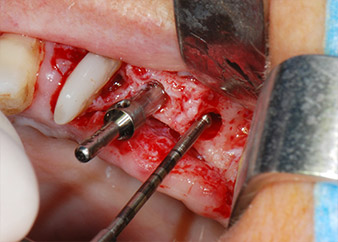

Implant beds were prepared at sites 25 and 26 with rotary instruments, used in a contra-angle handpiece with a 20 : 1 transmission ratio with an updated powerful implant motor (Implantmed, W&H) (Fig. 8).

The final preparation next to the sinus was again carried out with a piezoelectric instrument (Piezomed, insert S2).

Prior to implant placement, and following verification of an intact Schneiderian membrane (Fig. 9), the internal sinus floor was augmented at both implant sites by means of xenogeneic bone substitute material (Bio-Oss, Geistlich Biomaterials) (Fig. 10).